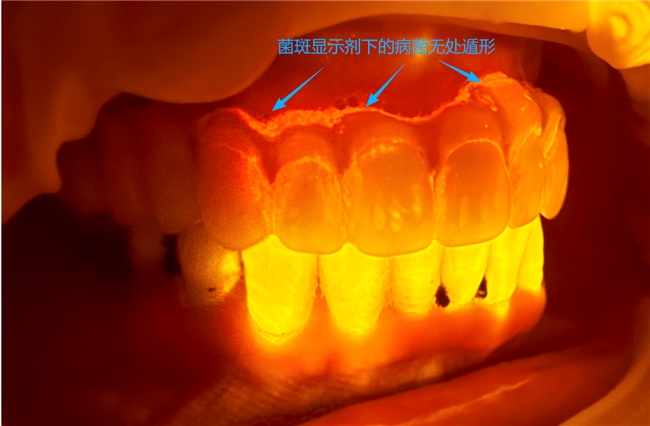

黎强对激光治疗的优势尤为认可:“用激光治疗牙周炎,不用打麻药,一次性搞定,不出血,疗效好,相比传统刮治方法,彻底避免了酸痛、出血等问题,提高了治疗效率。” 同时,鼎植还通过激光设备结合显微镜检测病菌,搭配荧光灯让菌斑可视化,让老百姓能直观看到口腔细菌感染情况,真正重视牙周问题。